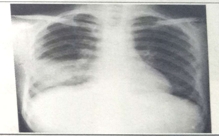

2022年临床助理医师实践技能考试影像诊断模拟题(2分)

2022-03-29